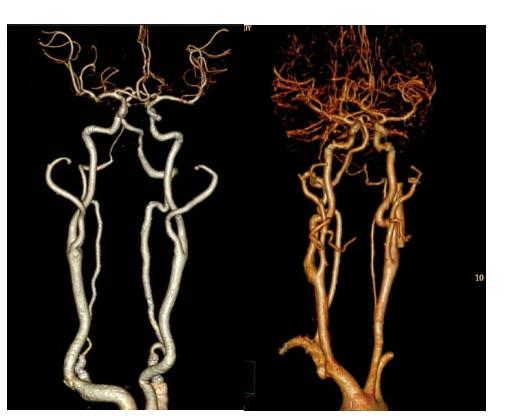

五.CT血管造影(CTA)

128层螺旋CT 血管成像技术是一种比较可靠、简便、经济而且安全的血管病变无创检查手段。可以很好的显示动脉血管的解剖变异,能够正确诊断动脉血管不同程度的狭窄,诊断重度以上的狭窄的敏感性与特异性均较高,CTA诊断血管闭塞的敏感性和特异性达到100%。

颈动脉成像

头颈部CTA

使用专用软件对血管狭窄进行分析